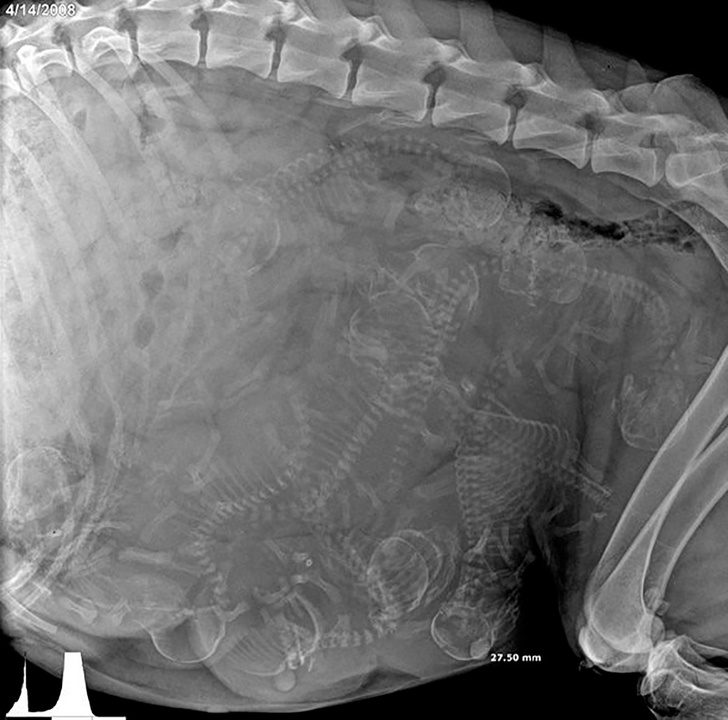

▼懷孕狗狗的X光片。